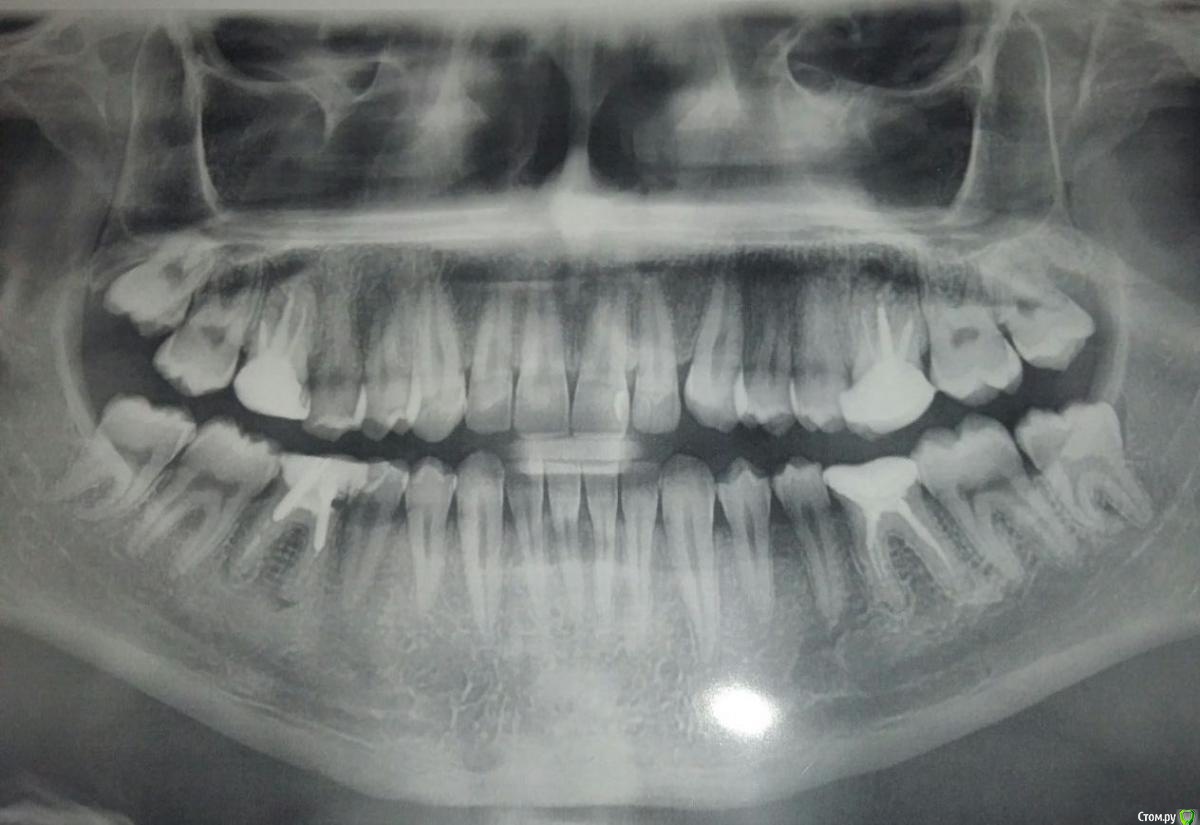

Vydra_Kus Опубликовано 15 мая, 2020 Поделиться Опубликовано 15 мая, 2020 Добрый день. Имеются гранулёмы с правой стороны у верхней и нижней шестёрки. Какой из вариантов лечения будет рациональнее: лечение через распломбировку каналов, имплантация, или удаление всех шестёрок с постановкой брекет-системы для сближения семёрки и восьмёрки. Ссылка на комментарий

St. Опубликовано 15 мая, 2020 Поделиться Опубликовано 15 мая, 2020 Добрый день. удаление всех шестёрок с постановкой брекет-системы для сближения семёрки и восьмёрки. У взрослых пациентов долго, рисковано и обычно не оправдано. лечение через распломбировку каналов, имплантация Если получится распломбировать и корни хорошие, то лечить. Если сильно разрушены то удаление и имплантация.То есть доктор смотрит после снятия коронок\ пломб\штифтов что отсталость от зуба и на основании увиденного принимает решение лечить или удалять. 1 Ссылка на комментарий